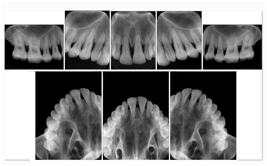

2. A patient requests cosmetic surgery to enhance their facial appearance. The case requires consultation between an orthodontist in New York and an oral surgeon in California. The cephalometric series of 2D projections constructed from the volumetric CT data that is used for the discussion is arranged by a Structured Display for transfer between the two practitioners.

Cephalometric Series Structured Display

Figure OO-2. Cephalometric Series Structured Display